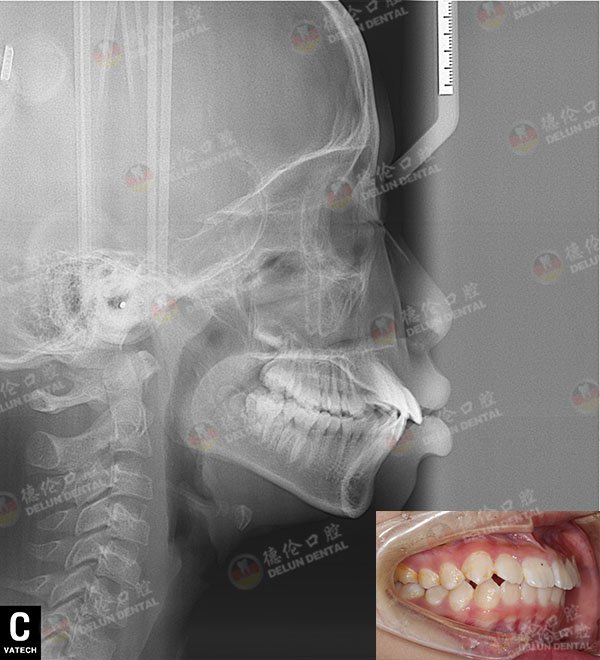

牙齿症状:上颌牙前突,牙列不齐

治疗方案:半隐形陶瓷托槽矫正

矫正前口内侧面照

这一下,沁曦的牙齿矫正就可以经过德伦团队的会诊以及方案制定,能够程度上保证矫牙舒适度与完成度。本身沁曦就正处于发育的高峰期,是一个非常有利与矫正的时期。考虑到沁曦本人作为一个孩子的敏感,以及面对镜头的需要,德伦专家一致决定为沁曦做半隐形陶瓷托槽矫正。

半隐形陶瓷采用航天民用特种透明陶瓷材料,颜色接近牙齿本色,精致小巧,不容易被发现,不含金属成分,相容性极好,佩戴舒适不磨损口腔。现在沁曦已经开始佩戴了矫治器,相信牙齿可以在科学合理的矫治力的牵引下,慢慢自动归位。